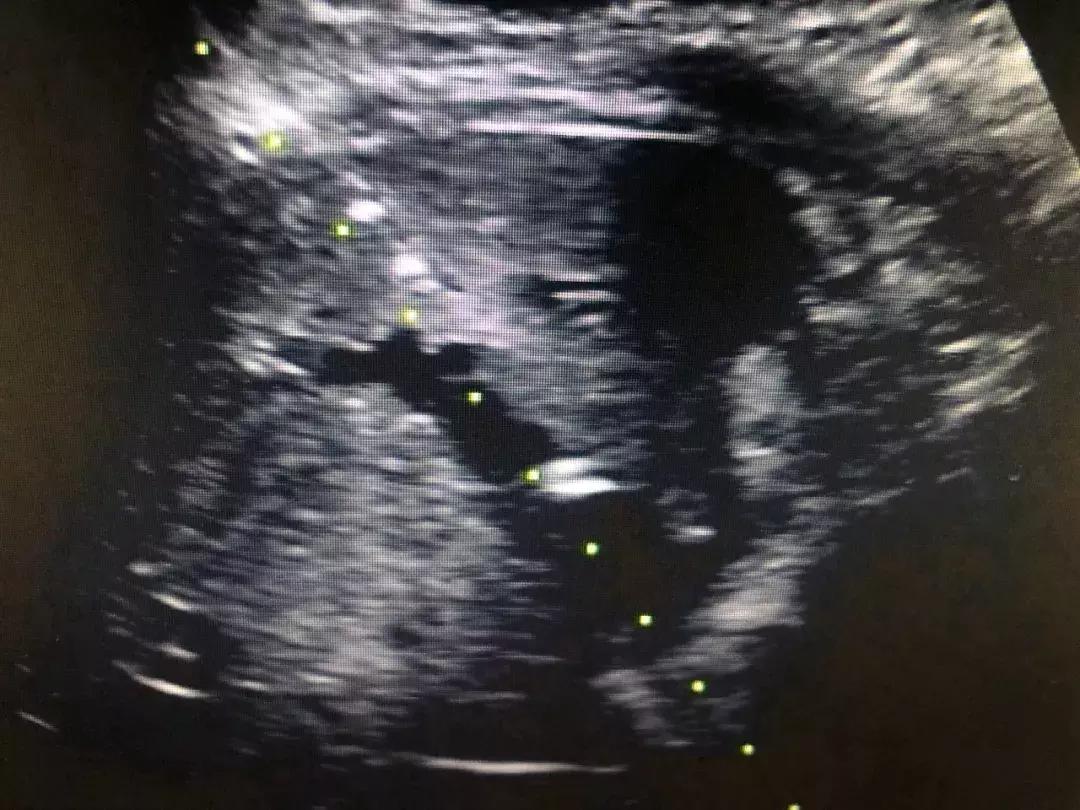

近日,一位75岁的胰头癌伴肝内转移的患者,肝内胆管明显扩张,肝功能差,黄疸指数高,无法行根治切除术,纠结的患者家属找到了西安市中心医院超声科,通过充分的术前评估,郑瑜主任等为其进行了超声引导下经皮肝穿刺胆管引流术(PTCD),随着大量的胆汁的流出,患者态势明显改善,各项指标趋于平稳。

超声引导下PTCD是在超声监测下,利用特殊穿刺针经皮穿入肝内胆管,再将外引流管置入肝内胆管,从而达到胆道内胆汁外引流,从而减轻黄疸,恢复肝功能,为进一步手术创造条件或者达到姑息治疗的目的,针对恶性梗阻性黄疸、急性胆管炎等疾病来说,PTCD是首选的治疗方案。

超声引导下经皮经肝胆道置管属于超声介入中难度较高的手术,以往因仪器、材料、经验等问题成功率较低,近年来我院超声科郑瑜主任团队经过不断的学习、实践与总结,进行专项技术攻关,同时提升了仪器性能,改进了技术流程,目前已完成83例,成功率达95%左右,基本上做到超声引导下“一针减黄”,操作时间基本控制在15分钟内。